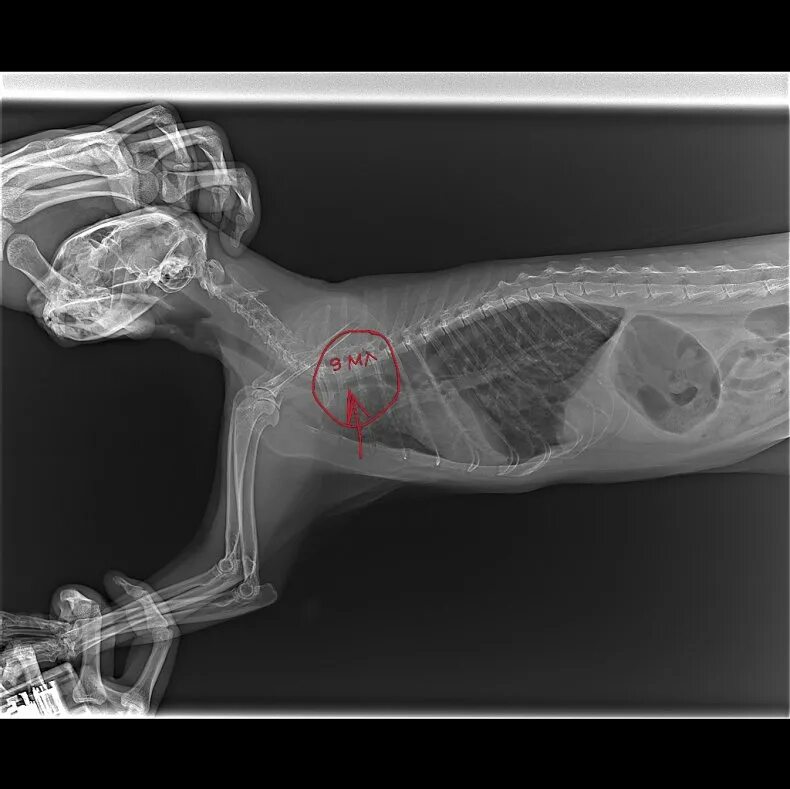

Астма у кота